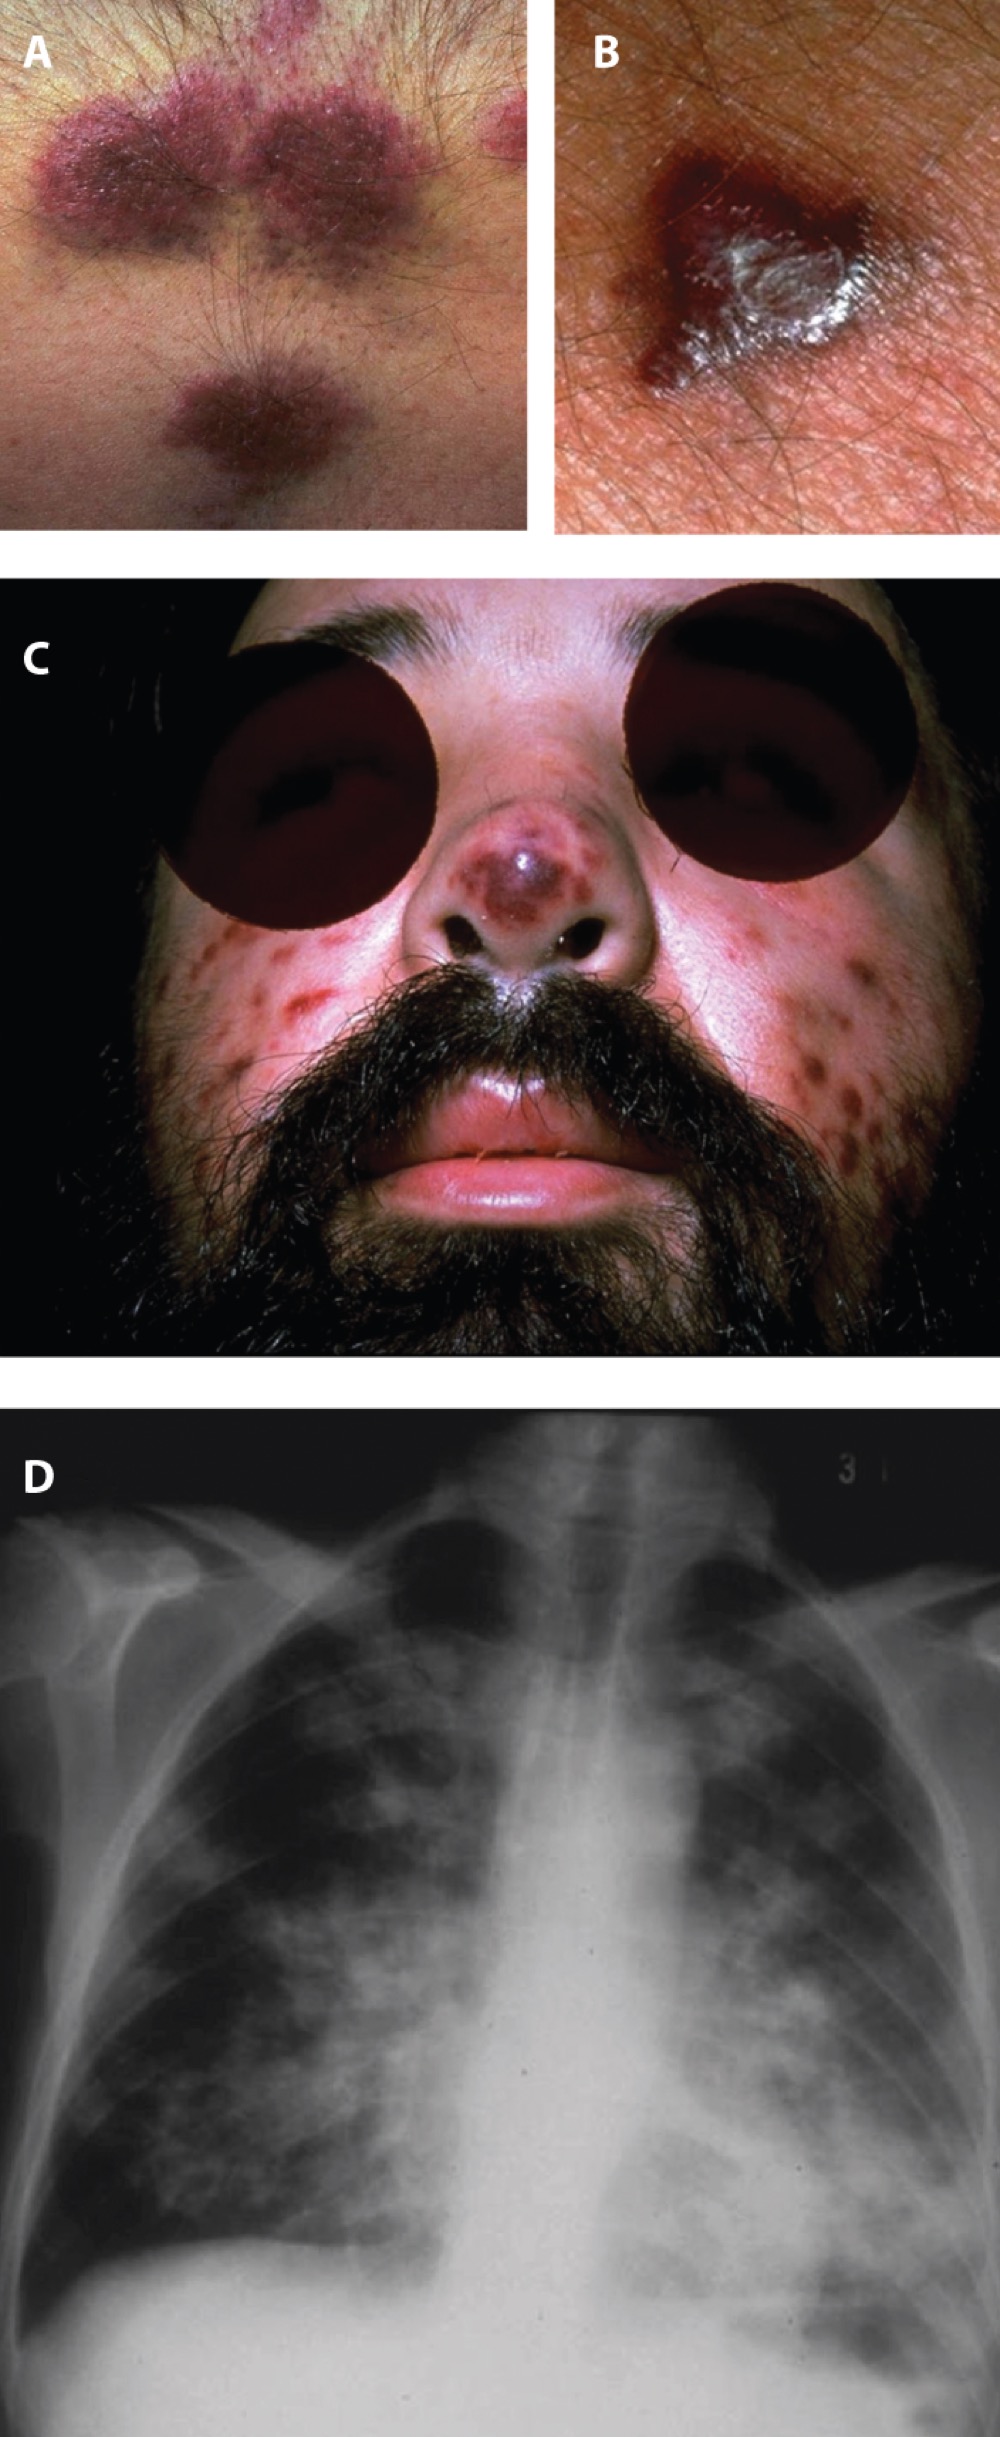

\

A

8

New cards

Which organism is causing this infection?

A. Staph aureus

B. Strep pneumoniae

C. Herpes simplex

D. Clostridium botulinum